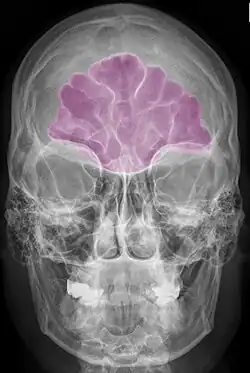

Stirnhöhle violett

Die Stirnhöhle (Sinus frontalis) ist eine der Nasennebenhöhlen (Sinus paranasales). Sie stellt einen mit Schleimhaut ausgekleideten Hohlraum im Stirnbein (Os frontale) dar, der mit dem mittleren Nasengang („Sinusgang“) der Nasenhöhle in Verbindung steht. Zusätzlich besteht eine Verbindung zu den Siebbeinzellen, die bei Pferden besonders geräumig ist, so dass beide Nebenhöhlen bei dieser Tierart auch als Sinus conchofrontalis zusammengefasst werden. Die Stirnhöhlen beider Seiten sind durch eine dünne Scheidewand (Septum sinuum frontalium) voneinander getrennt.